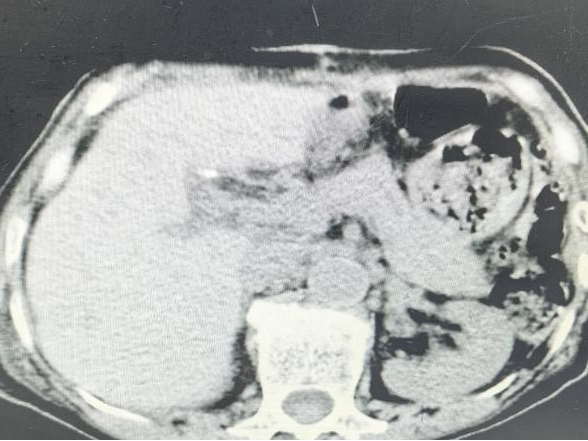

术前CT

送来医院一查,CT和磁共振片子上左肝内胆管和胆总管里密密麻麻全是结石,最大那颗跟核桃似的堵在那儿。肝内胆管结石、胆总管结石伴急性胆管炎、胆汁型肝硬化,老太太的皮肤和眼白都泛着黄。

主刀医生沿右肋缘做了个切口、逐层切开入腹探查——胆总管囊状扩张,结石像一座微型石林,层层叠叠卡在胆总管及肝内胆管,有的已经跟胆管壁长在一起,左半肝部分纤维化萎缩。团队果断进行手术:左半肝直接切除,这叫解剖性肝叶切除,沿肝脏天然分界线精准切割,该留的一寸不多切,该去的毫不含糊;胆囊一并拿掉;接着进行胆总管探查取石,随着取石钳将结石一颗一颗清理干净,术中探测oddi括约肌失能,于是同时行胆肠内引流,胆总管与空肠吻合改道手术,最后T管引流。